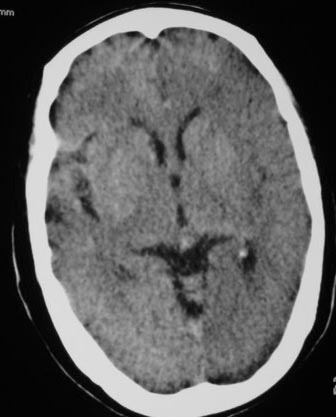

失语及右侧肢体无力3小时

左侧大脑半球与对侧相比较密度普遍密度降低,结合临床首先考虑是脑梗塞早期,必要时复查或mri。

左侧脑表面脑变窄,左外侧裂池受压变窄。

左侧大脑半球密度减低,左外侧裂消失。脑梗塞急性期

左侧侧裂池消失,脑沟变浅.典型的一侧大脑半球缺血改变.可以诊断:左侧大面积脑梗塞.

左侧大脑半球密度普遍降低,脑沟池消失,考虑大面积梗塞

左侧大脑半球大片密度减低影,脑沟变浅,外侧裂变窄,中线结构无明显移位。左侧大面积脑梗塞,大脑中动脉堵塞所致,愈后不好呀!应早期溶栓啊。

典型的左侧大脑半球早期缺血性脑梗塞(符合大脑前动脉、中动脉、大脑后动脉供血区。)

典型的左侧大脑半球缺血性脑梗塞早期表现[左侧大脑半球皮质密度减低与脑白质密度一致(脑皮质征),左侧豆状核轮廓模糊,密度与脑白质一致(豆状核征),结合临床有失语及右侧肢体无力3小时]。